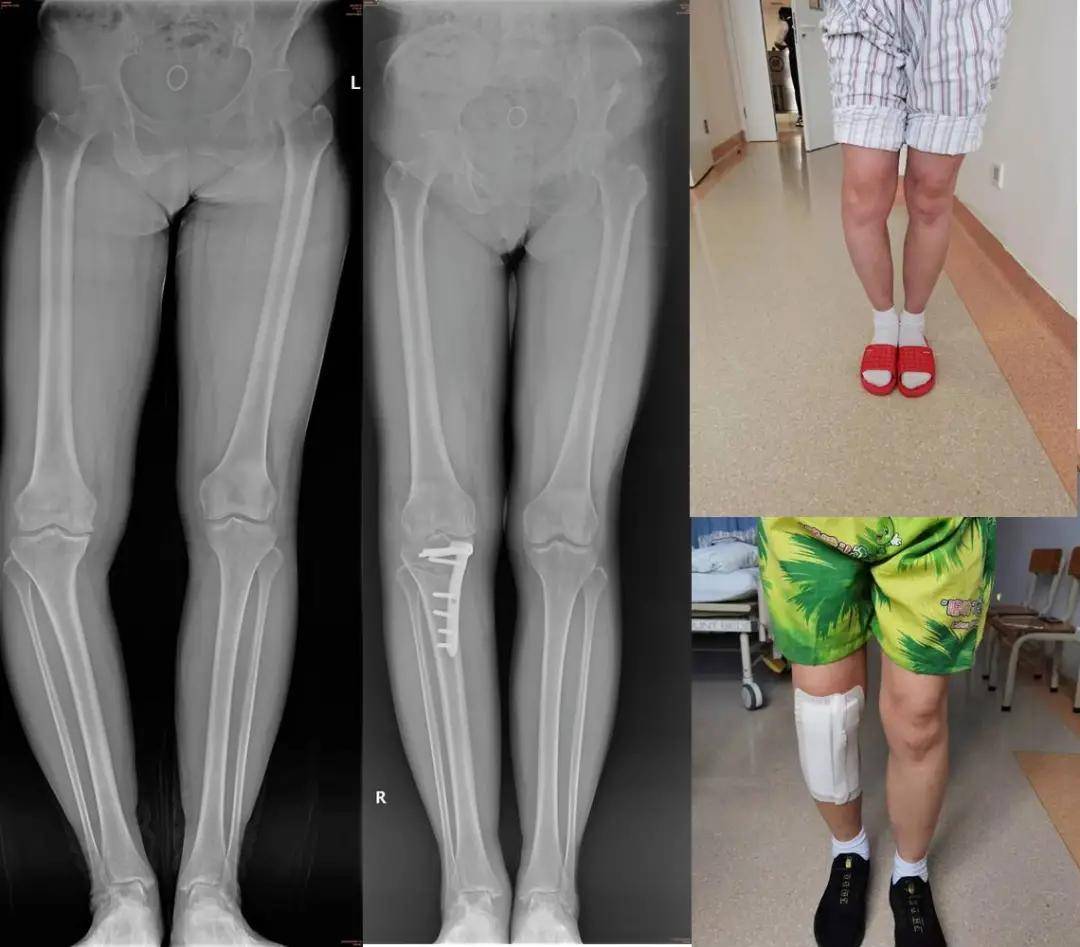

儿童骨骼先天发育不良,o型腿严重,胫骨高位截骨来拯救!

矫形术病情发展:患者从6年前起,患者逐渐出现了小腿的内翻畸形(o型腿)

o形腿胫骨高位截骨 完美矫正畸形